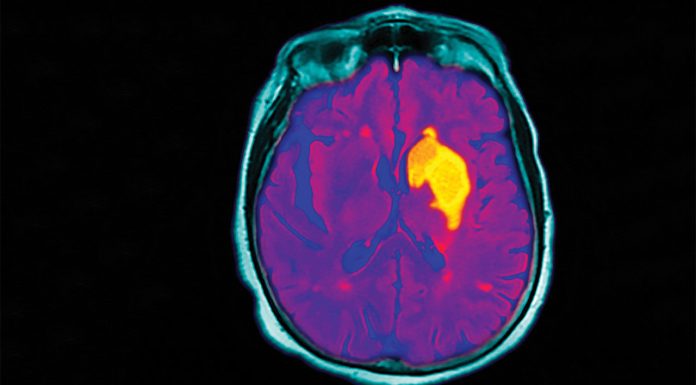

Guidelines for stroke management have been updated.

The time window for thrombolysis has been extended to 9 hours if brain imaging shows it will be...